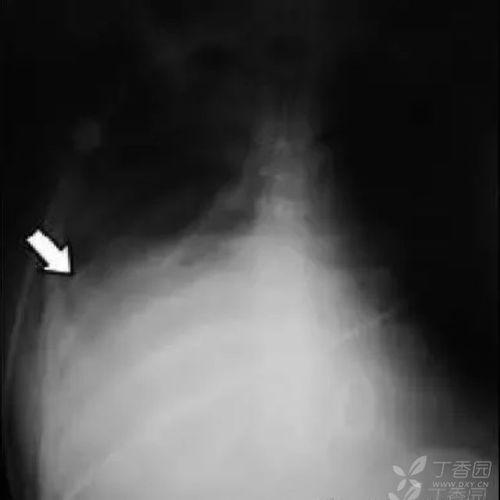

少量胸腔积液可以看到四边形征和正弦征,四边形征指胸腔积液时将胸膜

包裹性胸腔积液

胸腔积液胸片典型图片

胸腔积液片子图片